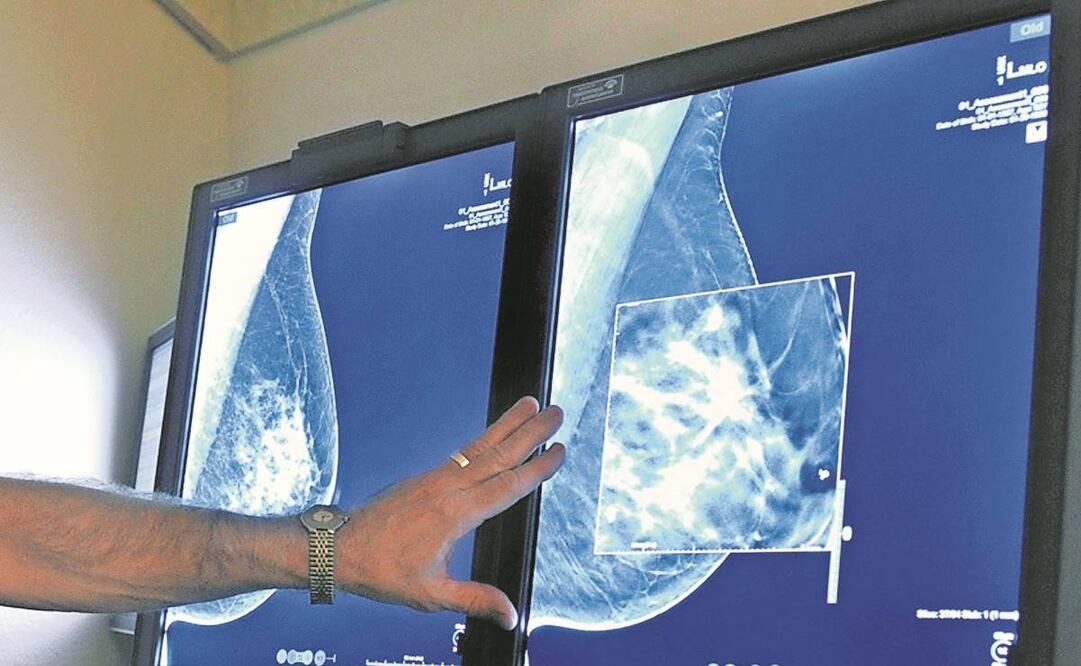

De acuerdo con los Centros para el Control y Prevención de Enfermedades de EU (CDC, por sus siglas en inglés), en 2019, el año más reciente del que se tienen estadísticas, en el país se enfermaron de cáncer de mama 264 mil 121 mujeres, de las que 42 mil 280 fallecieron. Un promedio de 130 por cada 100 mil mujeres en EU.

La estadística muestra que los casos anualizados van a la baja: cada año hay mejores respuestas de supervivencia en la nación para que una mujer diagnosticada con cáncer de seno siga viva.